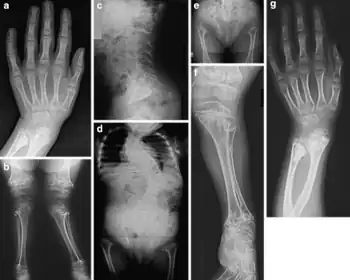

Spondyloepimetaphyseal dysplasia is a genetic condition affecting the bones.[1]